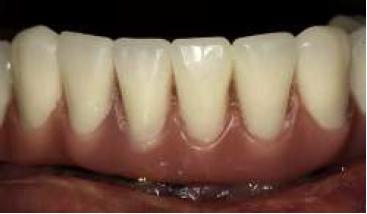

Al tercer día se realizó la instalación con torque manual y ajuste oclusal (figs. 13,14,15,16).

A los 10 días, luego de la cirugía, se citó a la paciente a control para realizar la retirada de la sutura11; se dio torque a los tornillos protésicos (10 N/cm) y se chequeó la oclusión nuevamente. Se ha seguido controlando a la paciente cada 6 meses, hasta cumplir 2 años desde la fecha de instalación de la aparatología, sin manifestar complicación alguna (figs. 17, 18, 19, 20, 21).

Se puede observar un control adecuado de biofilm por parte de la paciente.